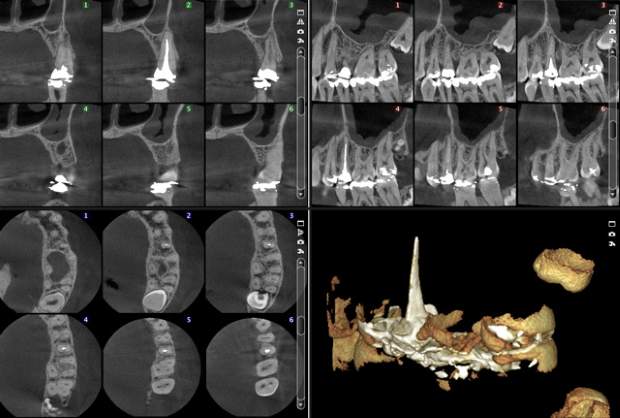

Bez redukcji szumów

Po użyciu filtra szumów Planmeca AINO

Bez usuwania artefaktów

Z użyciem algorytmu usuwania artefaktów Planmeca ARA

Planmeca ProMax 3D s Ø50x50 mm, rozmiar woksela 75µm

Planmeca ProMax 3D Mid Ø40x50 mm, rozmiar woksela 75µm